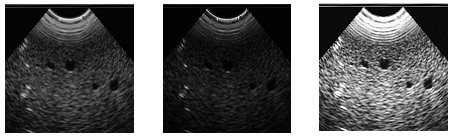

圖像融合是指將一個(gè)或一個(gè)以上的傳感器在同一時(shí)間,或不同時(shí)間獲取的關(guān)于某個(gè)具體場(chǎng)景的圖像或者圖像序列信…